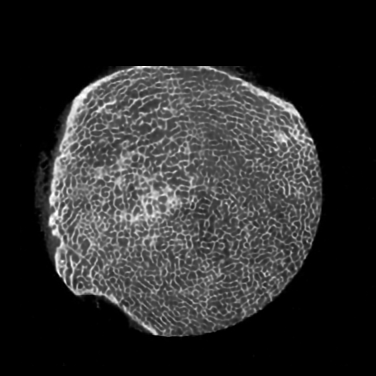

III-A1 Tibia dataset

This micro-CT image dataset reflects twenty-five fresh-frozen cadaveric ankle specimens which were removed at mid-tibia from 17 body donors (mean age at death ±plus-or-minus\pm SD: 79.6± 13.2plus-or-minus79.613.279.6\,\pm\,13.2 Y; 999 female). After the soft tissue were removed and the tibia was dislocated from the ankle joint, each specimen was scanned on a Siemens microCAT II (Preclinical Solutions, Knoxville, TN, USA) in the cone beam imaging geometry. The micro-CT parameters are briefly summarized as follows: a tube voltage 100100100 kV, a tube current 200200200 mAs, 720720720 projections over a range of 220220220 degrees, an exposure time of 1.01.01.0 sec per projection, and the filter backprojection (FBP) method was utilized to produce 28.8μm28.8𝜇𝑚28.8~{}\mu m isotropic voxels. Since CT images are not isotropic in each direction, for convenience of our previous analysis [70], we convert micro-CT images to 150μm150𝜇𝑚150~{}\mu m using a windowed sync interpolation method. In this study, the micro-CT images we utilized as HR images were prepared at 150μm150𝜇𝑚150~{}\mu m voxel size, as the target for SR imaging based of the corresponding LR images at 300μm300𝜇𝑚300~{}\mu m voxel size. The full description is in [70]. We target 111X resolution improvement.